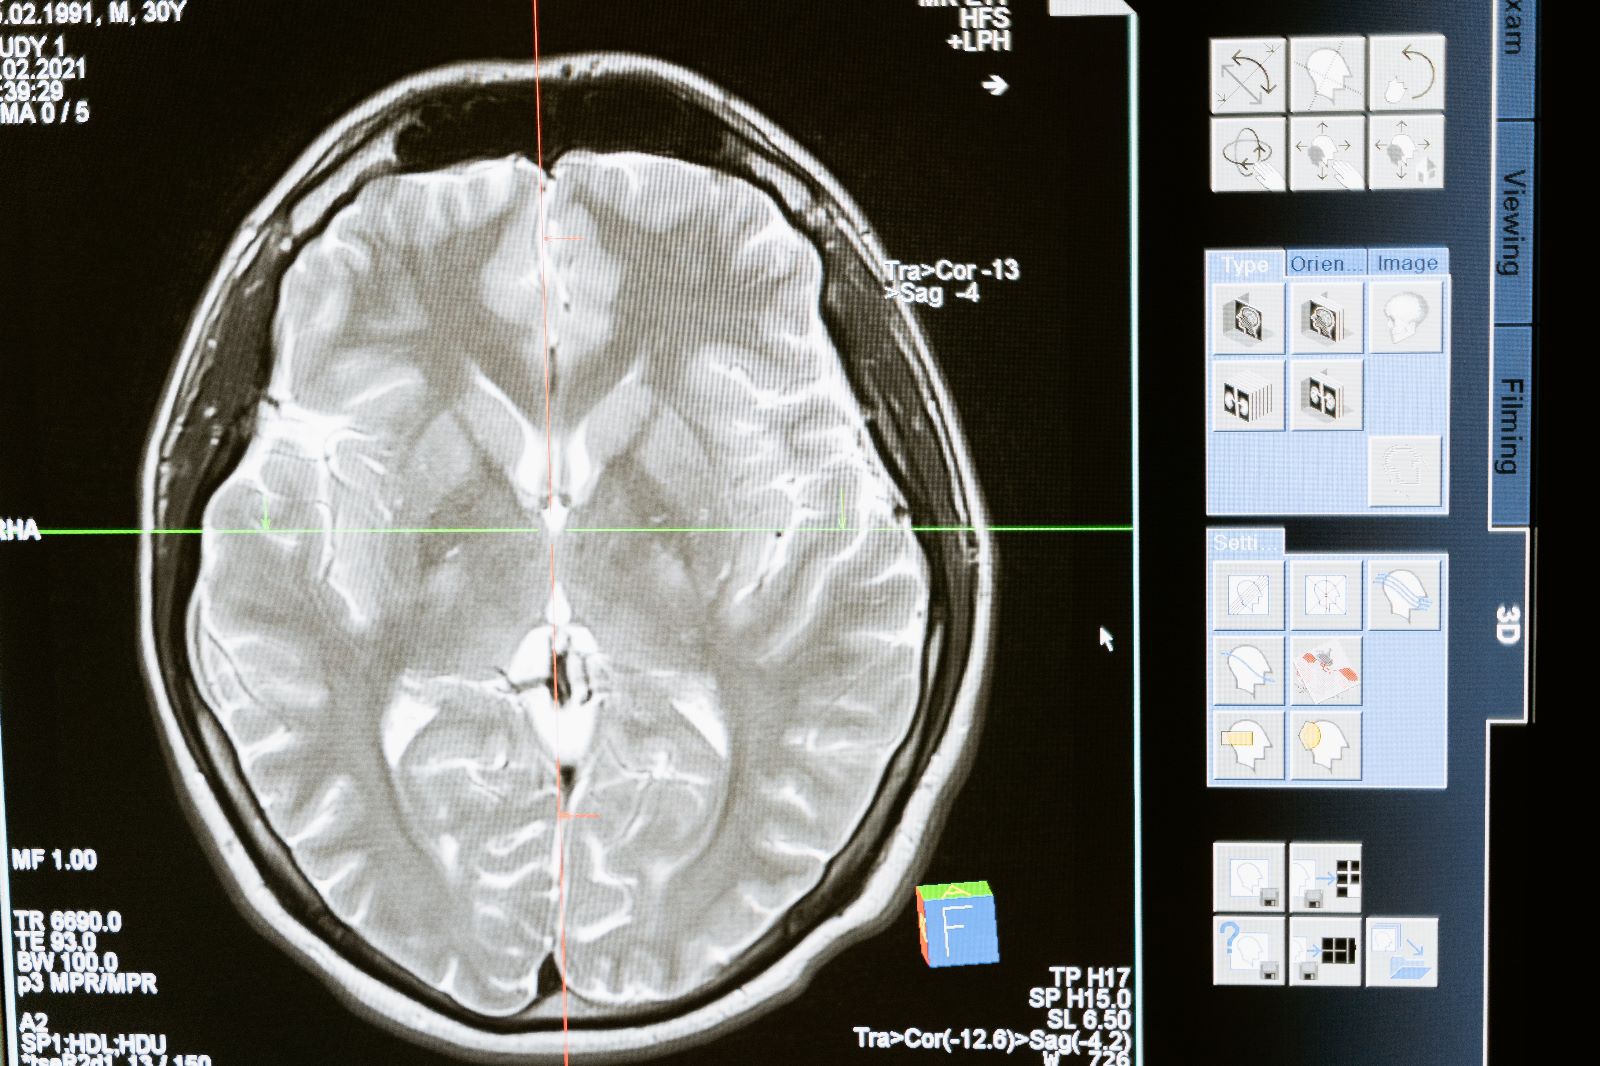

Peki TMS beyinde nasıl bir etki meydana getiriyor. Beynimizin belli bölgelerine herhangi bir zarar oluşturmadan verilen manyetik uyarılar kafa derisi ve kemik yapıyı mıknatıs etkisi ile geçiyor ve fonksiyonu bozularak hastalanmış beyin hücrelerini uyarıyor. Bu mıknatıs uyarısının etkisi beyin hücrelerinde elektriksel bir enerji oluşturarak bozulmuş olan düzeni ve ahengi eski haline getirecek bir dizi hormonal ve kimyasal faaliyetin de sebebi oluyor.

Beynimizin mükemmel bir yaratılışla yaratıldığını söylemeye gerek yok .Bu mükemmellik içerisinde TMS tedavisi ile onu günümüzün anlaşılır tabiri ile resetlemek yada formatlamak mümkün oluyor. Onun mükemmel olarak çalışmaya devam etmesi için illa dışardan çeşitli kimyasal formüllere ilaçlara da belki ihtiyacı yok..